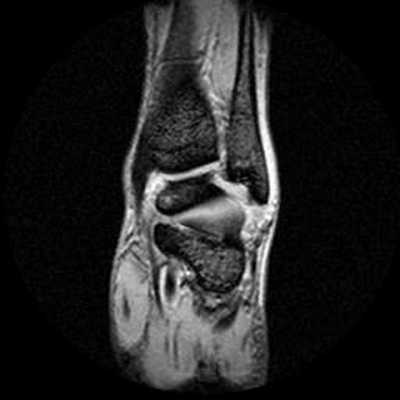

Расшифровка

На серии МР-томограмм визуализированы структуры левого голеностопного сустава. Соотношения в голеностопном, подтаранном суставах не нарушены, патологического выпота в полости голеностопного сустава не выявлено. Синовиальная оболочка не дифференцируется. Хрящевое покрытие голеностопного, подтаранного и таранно-ладьевидного суставов неравномерно истончено. Суставные полости голеностопного, подтаранного и таранно-ладьевидного суставов слева умеренно неравномерно сужены.

Медиальные отделы: патологических сигналов от медиальной лодыжки не выявлено. В краевых медиальных отделах блока таранной кости субхондрально отмечается локальный участок эрозирования размером ~ 2-3мм, без патологических изменений в смежных трабекулярных отделах. Дельтовидная связка определяется на всем протяжении, сигнал от связки неоднородный, общее натяжение связки сохранено. Сухожилия длинного сгибателя большого пальца, длинного сгибателей пальцев, задней большеберцовой мышцы однородной структуры.

Латеральные отделы: патологических сигналов от латеральной лодыжки не выявлено. Передняя и задняя нижние межберцовые связки сохранены, межберцовый синдесмоз равномерный на всем протяжении. Передняя таранно-малоберцовая связка определяется на всем протяжении, истончена, отмечается слабоинтенсивное повышение сигнала от связки, общая целостность сохранена. Задняя таранно-малоберцовая связка не изменена. Пяточно-малоберцовая связка прослеживается на всем протяжении, типичной структуры. Структура сухожилий малоберцовых мышц однородная, определяется скопление жидкости перитендинозно сухожилиям короткой и длинной малоберцовой мышц.

Задние отделы: определяется удлинение латерального бугорка заднего отростка таранной кости, без патологических изменений сигнала от прилежащих отделов жировой клетчатки, отмечается локальное скопление однородной жидкости в данной зоне. В задних отделах пяточной кости, в области пяточного бугра, субкортикально отмечается локальный участок эрозирования размером ~ 3-4мм, без патологических изменений в смежных трабекулярных отделах. Определяется шиповидное костное разрастание в задненижних отделах пяточной кости, на уровне прикрепления подошвенной фасции и короткого сгибателя пальцев, без патологических изменений сигнала от данной фасции. Пяточное сухожилие однородной структуры. Клетчатка Кагера без особенностей. Тарзальный канал не изменен.

Передние отделы: сухожилия передней большеберцовой мышцы, разгибателей пальцев стопы и большого пальца равномерны по толщине и интенсивности сигнала. Плюсневая пазуха без особенностей.

Заключение: МР-картина частичного повреждения дельтовидной и передней таранно-малоберцовой связок. МР-признаки деформирующего артроза голеностопного, подтаранного и таранно-ладьевидного суставов 1-2ст. Теносиновит сухожилий малоберцовых мышц.